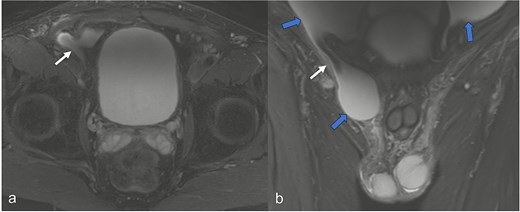

A 52-year-old male patient presented for surgical treatment of a recurrent hernia in the right groin. The preoperative sonography revealed a hernial orifice with a diameter of ~1 cm. In addition, there was clear ascites with a collection of fluid in the spermatic funiculus and a suspected mural tunica vaginalis. A subsequent magnetic resonance imaging (MRI) examination of the pelvis showed a similar picture (Fig. 1). Due to the suspicious appearance of the tunica vaginalis, the recurrent hernia was not repaired at that time. In the renewed physical examination and history taking, the patient reported not only the familiar painful feeling of pressure in the area of the known inguinal hernia but also an increasing feeling of fullness over the entire abdomen. He had also lost 3 kg in weight in the last two months. He had been professionally exposed to asbestos while working as a master electrician in old houses. In the blood count, the C-reactive protein was slightly elevated at 1.88 mg/dl, the thrombocytes at 456 000/μl and the leukocytes at 12 000/μl. The subsequent computed tomography (CT) thorax and abdomen revealed a peritoneal carcinomatosis with ascites without evidence of a primary tumor (Fig. 2). An ascites puncture with subsequent cytological analysis revealed no pathological findings. The subsequent diagnostic laparoscopy revealed a four-quadrant metastasis with nodular structures on the peritoneum (Fig. 3) and the greater omentum. Biopsies taken from the peritoneum and greater omentum revealed a malignant high-grade epithelioid mesothelioma of the peritoneum (Fig. 4). After the tumor conference decision, another laparoscopy was performed to reduce the tumor tissue, after which the affected greater omentum and part of the peritoneum were removed. Hyperthermic intraperitoneal chemotherapy (HIPEC) was then carried out, which was well tolerated and led to a complete remission during the 24-month follow-up period.

In the MRI examination of the pelvic region, the fat-suppressed, fluid-emphasized imaging in the axial section (a) shows a hernial orifice of ~1 cm (white arrow) and in the cronar section (b) the hernial orifice (white arrow) with ascites in the lesser pelvis and in the hernial sac/funiculus spermaticus (blue arrows).